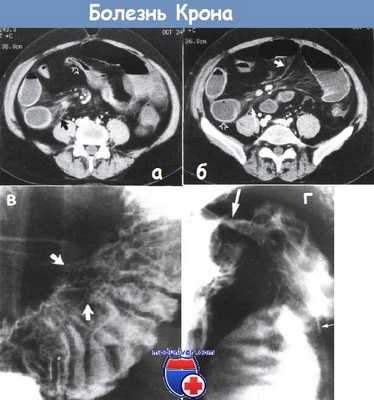

(Слева) На сагиттальном срезе проиллюстрированы типичные признаки болезни Крона: сегментарное утолщение стенки тонкой кишки, гиперемия слизистой оболочки, воспаление всех слоев стенки в сочетании с глубокими язвами га, избыточное кровенаполнение брыжеечных сосудов, а также фиброзно-жировая пролиферация.

(Справа) На КТ, выполненной юноше 19 лет в острой фазе болезни Крона, определяется интенсивное контрастное усиление слизистой оболочки, утолщение стенки и сужение просвета терминальных отделов подвздошной кишки. (Слева) На КТ у этого же пациента определяется воспаление терминальных отделов подвздошной кишки, наряду с фиброзно-жировой пролиферацией брыжейки и перенаполнением кровью прямых сосудов.

(Справа) На рентгенограмме тонкой кишки с бариевым контрастом, выполненной этому же пациенту, определяется поражение терминальных отделов подвздошной кишки с наличием поперечных и продольных язв слизистой оболочки (придающих ей вид «булыжной мостовой»), а также сужение просвета кишки. Визуализируются как минимум два свищевых хода. Традиционные рентгеновские исследования с бариевым контрастом сохраняют свою ценность для оценки стриктур, фистул и свище.